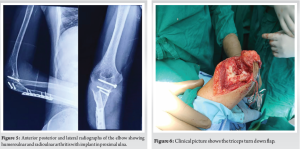

A 31-year-old male visited our outpatient department with complaints of right elbow pain on movement and restricted movements affecting his activities of daily living. He gave a history of road traffic accident 2 years before in which he had sustained a right-sided severely comminated proximal humerus fracture (Fig. 1) and right-side compound ulna proximal third shaft fracture with olecranon comminated fracture (Fig. 2). He underwent open reduction and fixation for proximal humerus (Fig. 3), olecranon and ulna fracture. 12 months post-surgery the proximal humerus implants were removed and the fracture was malunited (Fig. 4).

On presenting to us his range of motion in the elbow was restricted to 70–80° of elbow flexion and forearm fixed in mid pronation. He had restricted shoulder movements but his main concern was restricted movement of the right elbow affecting his activities of daily living. His radiographs showed post-traumatic arthritic changes in the right elbow with implants in situ (Fig. 5). Looking at his functional demands we decide to take him up for interposition arthroplasty of the right elbow once he was medically cleared for surgery.